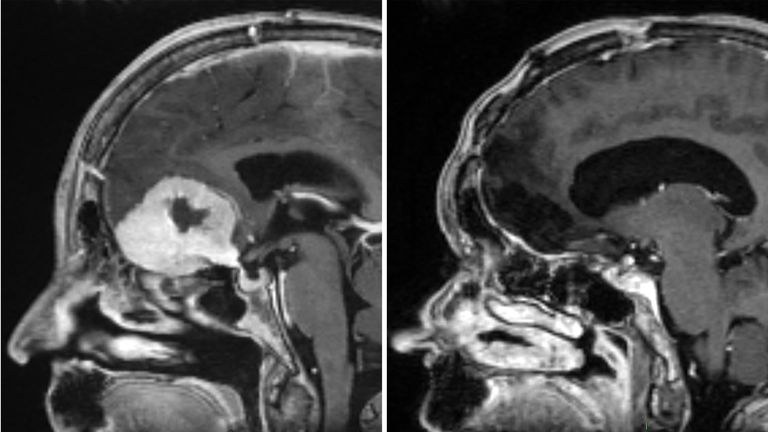

Home Tech News Surgeon removes large brain tumours through patients’ eyebrows in ‘world first’